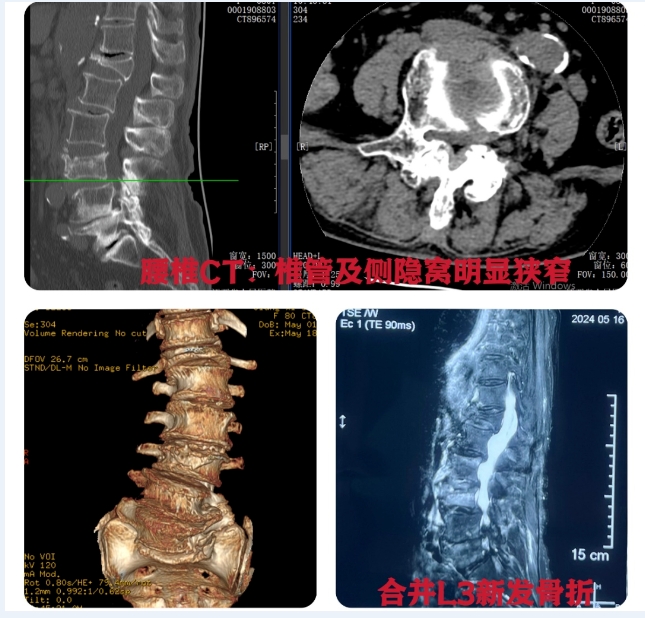

81岁的黄奶奶1年前开始出现行走后右下肢疼痛,当时并未引起重视,导致疼痛症状越来越重,走几步就酸胀难忍,生活无法自理。半个月前扭到腰后更是出现剧烈腰痛,情况更是雪上加霜。5月17日,黄奶奶在家属的陪同下辗转到江西省人民医院(南昌医学院第一附属医院)骨科一区办理了住院。主任医师肖强接诊后发现患者整个腰椎明显变形,脊柱侧弯合并严重退变增生,容纳神经的结构已变得非常狭窄,这是导致她大腿疼痛的罪魁祸首;同时,黄奶奶合并严重骨质疏松导致腰椎(L3)新发骨折,这是导致她近期出现的严重腰痛主要原因。

肖强团队对黄奶奶的病情进行了仔细的分析讨论,认为想要解决其长期的腿痛问题,就要将骨性狭窄的椎管和侧隐窝完全打开,而她的腰椎退变增非常严重,以往需要在开放手术条件下才能进行有效处理,但黄奶奶高龄,骨质疏松严重,开放手术的风险及并发症发生率太高。